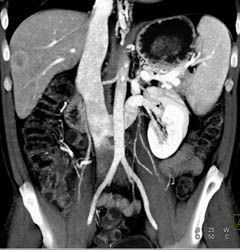

Diagnosis

Hepatoma